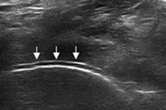

二、清晰显示软骨表面尿酸盐结晶沉积状况 判断痛风所属病期

肌骨超声可通过高清影像图判定软骨表面有无出现一条与强回声骨皮质平行的线样强回声,即“双轨征”这一痛风性关节炎特征性表现,判定疾病所属。当尿酸盐粘附并沉积于漂浮的滑膜上时,超声检查可在关节腔内发现漂浮的高亮回声;而当尿酸盐长期沉积于韧带上时,在超声中即显示条带状的略高回声(韧带)中出现高回声点、高回声带或高回声团块(尿酸盐),从而判断痛风病情处于哪一时期。

“双轨征”

跖趾关节软骨表面可见高回声不规则增强的软骨滑膜边缘线,呈“双轨征”。

高回声带

软骨表面回声增强,与深面的骨性关节面强回声线形成“双轨征”。